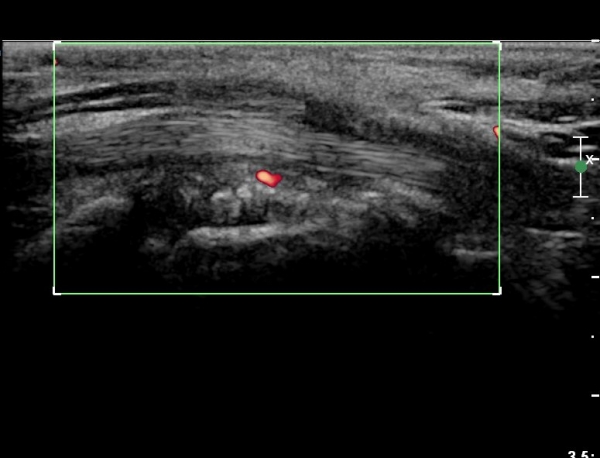

¼Õ¸ñ ºÎÀ§ Ⱦ´Ü¸é°Ë»ç¿¡¼ ¿ä°ñ°ú ¿ù»ó°ñ Àü¹æ¿¡ ¼®È¸È¼º À½¿µÀÌ Á¸ÀçÇϰí Àü¹ÝÀûÀÎ ¼öÁö ±¼°î°ÇÀÇ ºñÈÄ, Á¤Á߽ŰæÀÇ ºÎÁ¾°ú

ÈûÁÙ ¹× Á¤Á߽ŰæÀÇ Ç¥ÃþÀ¸·Î ÀüÀ§°¡ °üÂûµÈ´Ù, (»çÁø 1 ), ÆÄ¿öµµÇ÷¯°Ë»ç¿¡¼ Ç÷·ùÁõ°¡°¡ °üÂûµÊ´Ù(»çÁø 2)..